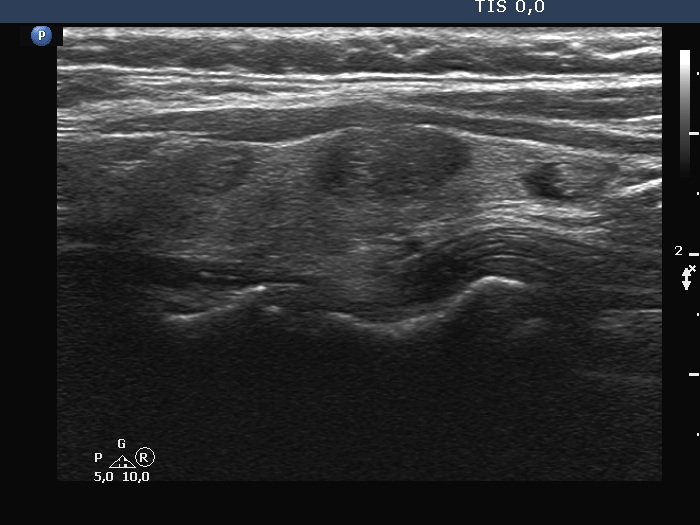

Follow-up investigation 6 years later (ultrasonographic picture 10)

Right lobe, longitudinal scan